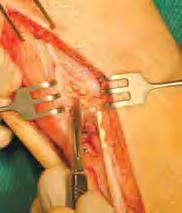

Rycina 6.12. Uwidoczniony śródoperacyjnie 12-centymetrowy ubytek w ciągłości

ścięgna – pacjentka leczona zachowawczo iniekcjami z glikokortykosteroidów

Ku przestrodze – opis przypadku

Zdjęcie śródoperacyjne – widoczne złogi steroidowe